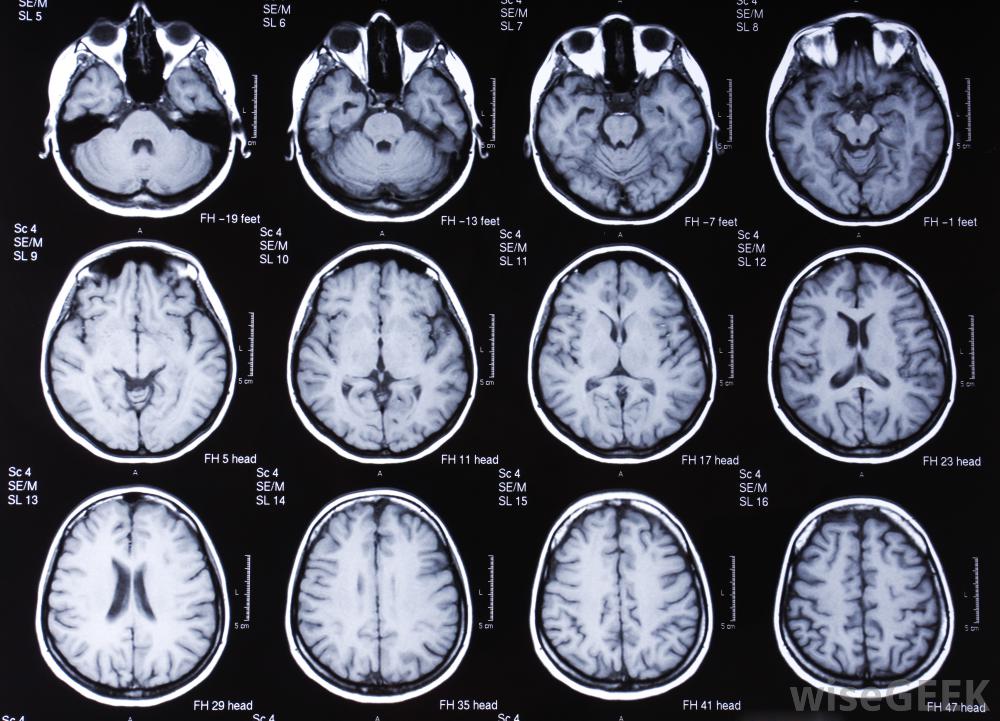

对大脑进行MRI扫描核磁共振成像通常用于识别潜在损伤或病理组织的存在。原因可能包括创伤性损伤(如肌肉拉伤)和更微妙的问题(如可能的癌症)。在这些情况下,传统的X射线甚至计算机断层扫描(CT)都不理想。MRI图像,它是通过使用射频波而不是电离辐射产生的,它更适合于软图像的渲染,非骨组织。

核磁共振成像允许对大脑结构进行可视化。